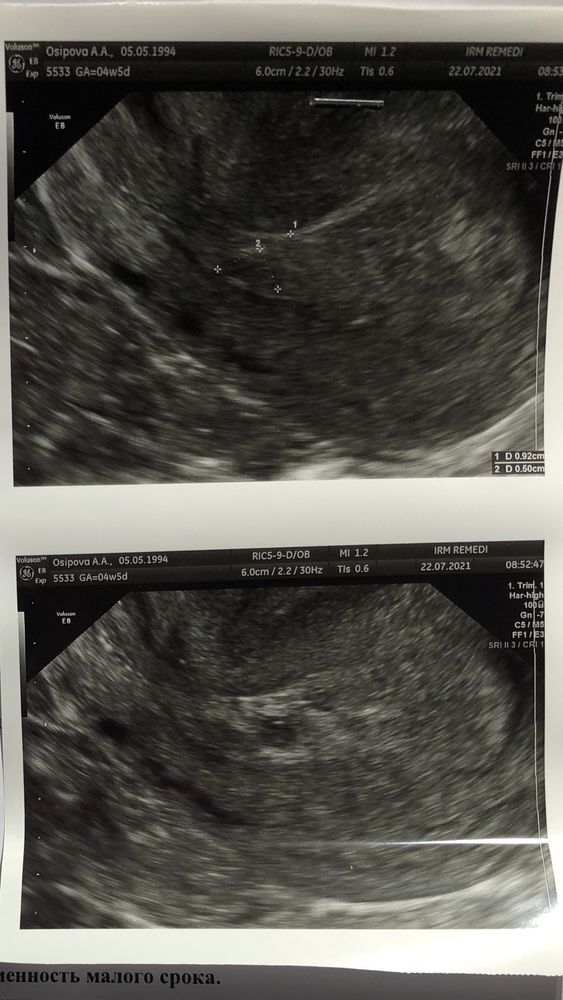

Добрый день, девочки! Сходила на УЗИ, сказали две новости: ПЯ 5 мм, ЖМ 2,3 мм. Эмбриона пока не визуализируется. Но… ПЯ находится в нижней трети полости матки. Выдали больничный на лежачий режим. Грозит это прерыванием беременности или бывало такое у кого с благоприятным исходом? Расскажите, пожалуйста!

22.07.2021